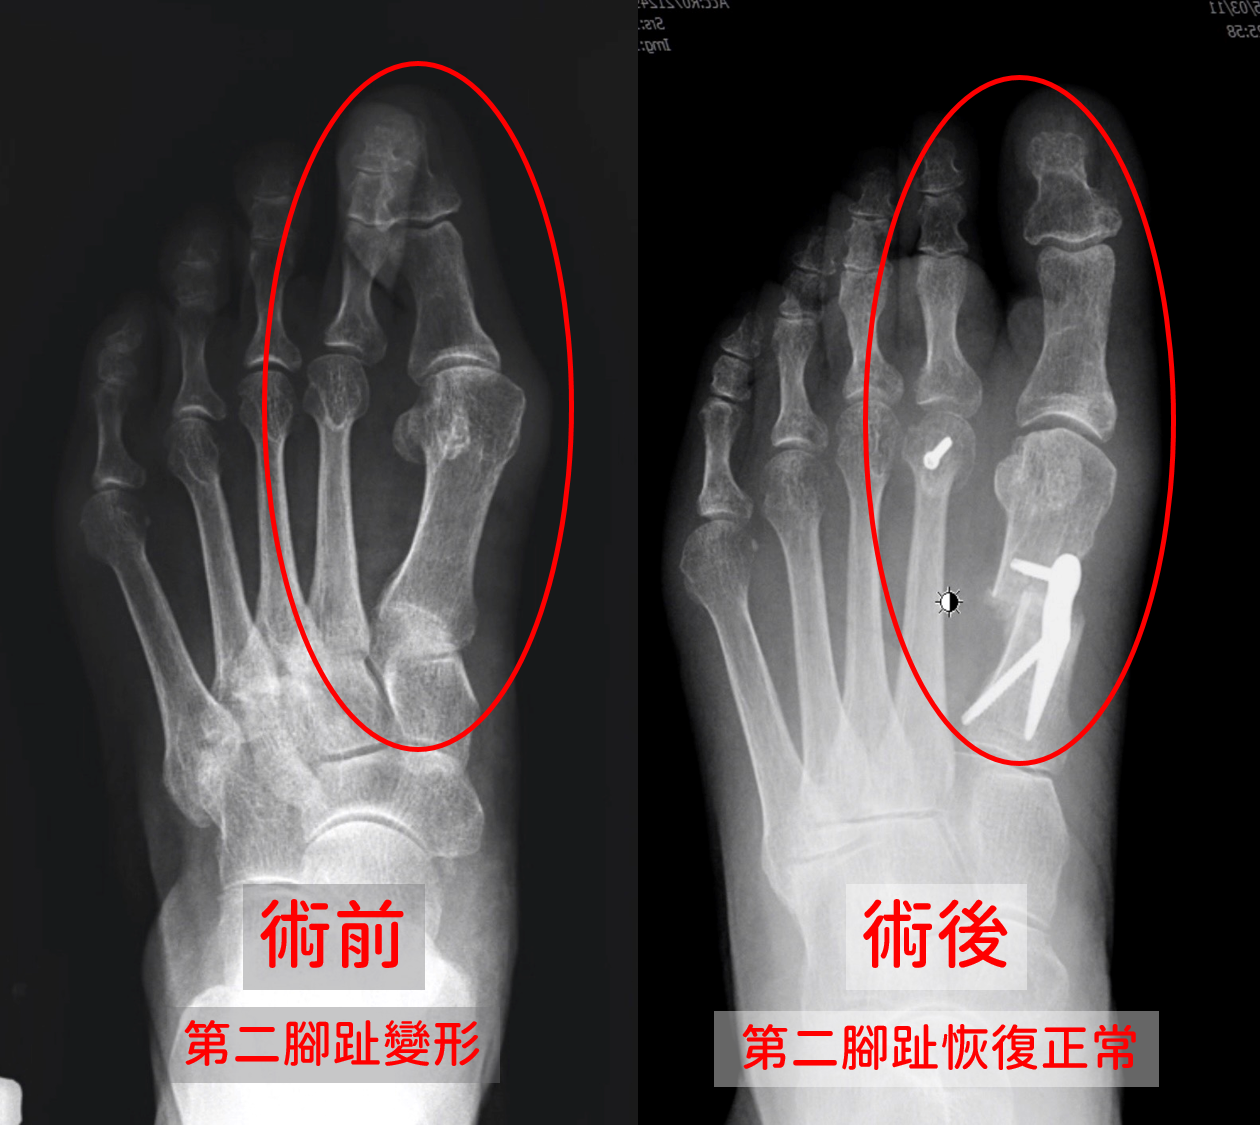

新竹一名68歲女性長期受拇指外翻困擾,近來左腳拇指變形惡化,導致第二腳趾被擠壓翹起,形成爪狀趾變形,腳底也長出厚繭伴隨劇烈疼痛,行走困難。經中國醫藥大學新竹附設醫院骨科楊子正醫師診斷,為「拇指外翻合併第二腳趾變形及蹠痛症候群」,透過微創骨矯正手術,短短30分鐘解決長年病痛,患者術後當天即可下床行走,隔日出院,恢復良好。

此次患者因第二腳趾出現爪狀趾交叉趾變形,是因為拇趾外翻持續擠壓,導致第二趾關節失衡而翹起、偏位,進而產生腳底過度受壓,導致蹠骨處長出厚繭並產生蹠痛,求助於中醫大新竹附設醫院骨科團隊,經過仔細檢查後,楊醫師採用微創拇趾外翻截骨矯正術,搭配第二腳趾蹠骨縮短與軟組織重建手術,根據患者變形嚴重度調整矯正幅度及重建方式。手術時間約30分鐘,當天即可下床,術後無需石膏固定,並可盡早開始足部關節復健訓練,幫助患者快速恢復正常生活機能。